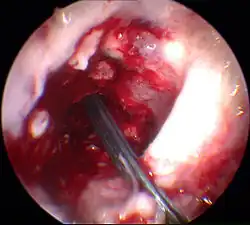

Déroulement typique de la reconstruction du ligament croisé antérieur

L'exemple présenté ci-après décrit le déroulement de la reconstruction du LCA par transplantation autologue de tendons semi-tendineux et gracile. Jusqu'aux années 1980, l'opération ouverte classique du LC était accomplie selon le procédé mis au point par Erwin Payr (de). Depuis, presque toutes les reconstructions de LC sont faites de façon peu invasive par arthroscopie[190],[266]. Ce n'est qu'exceptionnellement, par exemple pour des blessures très complexes du genou, que l'on pratique une opération ouverte.

Arthroscopie

L'opération proprement dite commence par l'introduction de l'arthroscope dans le genou du patient. Ceci permet de confirmer définitivement le diagnostic de rupture de LC. Les autres blessures, en particulier celles des ménisques, peuvent être soignées avant la reconstruction du LC.

Élimination des restes de ligament croisé et percement des canaux osseux

Les restes du LCA rompu sont éliminés sous arthroscopie. Pour cela, on utilise un outil motorisé de découpe et d'aspiration. À l'aide d'un appareil à positionner, la position pour le percement d'un canal à travers la tête du tibia est déterminée, et le trou est fait. La même procédure est appliquée au percement à travers le fémur. Ce canal se rétrécit vers le haut et a une longueur d'environ 35 mm. La partie plus large de ce canal est destinée à recueillir le transplant, la partie étroite à faire passer l'accrochage du transplant.